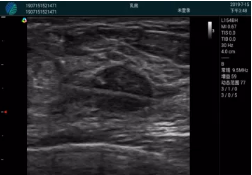

清晰顯示孕囊,通過(guò)軟件包計(jì)算孕齡7w+6d

M20實(shí)時(shí)引導(dǎo),術(shù)中清晰顯示孕囊被破壞和抽吸針的過(guò)程,清晰顯示吸引針

抽吸結(jié)束后縱切子宮,孕囊已被完全抽吸,未見(jiàn)明顯殘留

橫切子宮,發(fā)現(xiàn)右側(cè)宮腔靠近宮角處有少許脫模樣殘留

M20引導(dǎo)下,抽吸針找到右側(cè)宮角處再次清掃

二次抽吸后再次進(jìn)行超聲檢查,宮腔未見(jiàn)殘留,宮腔線(xiàn)清晰顯示